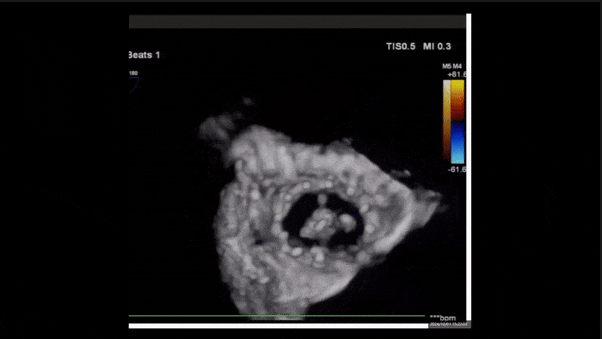

術(shù)后即刻返流三維

術(shù)后三維超聲

術(shù)后即刻經(jīng)食道超聲可見,三尖瓣假體瓣膜位置合適,牛心包瓣葉運(yùn)動狀態(tài)良好,開閉正常,瓣周及瓣葉對合緣處未見明顯返流,心電圖及心包狀態(tài)較術(shù)前無明顯變化。